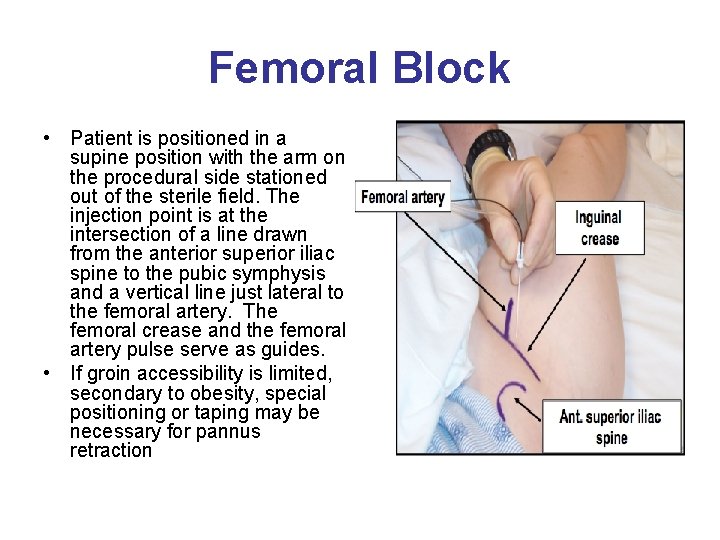

Femoral Block • Patient is positioned in a supine position with the arm on the procedural side stationed out of the sterile field. The injection point is at the intersection of a line drawn from the anterior superior iliac spine to the pubic symphysis and a vertical line just lateral to the femoral artery. The femoral crease and the femoral artery pulse serve as guides. • If groin accessibility is limited, secondary to obesity, special positioning or taping may be necessary for pannus retraction